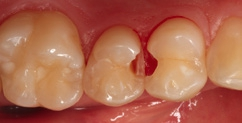

Fall 6 Minimalinvasive Behandlung von tiefen Approximalläsionen an Zähnen 14 und 15

Bei dem 26-jährigen, frisch approbierten Zahnarzt imponierte eine untypisch hohe Kariesaktivität mit etlichen, teils sehr tiefen Approximalläsionen, die einer therapeutisch- restaurativen Intervention bedurften. An den Zähnen 14 und 15 zeigte sich eine auffällige Transluzenzänderung des Zahnschmelzes, was immer ein untrügerisches Zeichen für eine darunterliegende, bereits in das Dentin penetrierte Karies darstellt (Abb. 23). Die Abbildung 24 verdeutlicht – noch während der Exkavation – das Ausmaß des vorgefundenen Defektes. In der Abbildung 25 sind die vollständigen Kavitäten, bereits mit Teilmatrizen und einem Palodent V3-Spannring isoliert, erkennbar. Durch den hervorragenden Separationsdruck dieser Art von Spannringen können benachbarte Approximalläsionen in der Regel problemlos zeitgleich versorgt Anwerden. Nach der adhäsiven Vorbehandlung – im vorliegenden Fall mit einem klassischen Mehrflaschen-Etch&Rinse- Adhäsiv (Abb. 26) – erfolgte die Versorgung mit SDR flow+ in der Farbe A3 in zwei horizontalen Inkrementen. Beide Inkremente, die eine Dicke von ca. 3 mm aufwiesen, wurden für je 40 Sekunden gemäß Herstellerangaben polymerisiert. Eine gemeinsame abschließende Polymerisation für 20 Sekunden nach Entfernen der Matrizen ergänzte das Aushärtungsprotokoll. Die Abbildung 27 zeigt die Situation direkt nach Ausarbeitung und Politur, die Abbildung 28 bei einer weiteren Nachkontrolle nach drei Monaten. Es zeigte sich nach der Rehydrierung der Strukturen eine deutlich bessere Farbadaptation als initial, unmittelbar nach dem Legen.